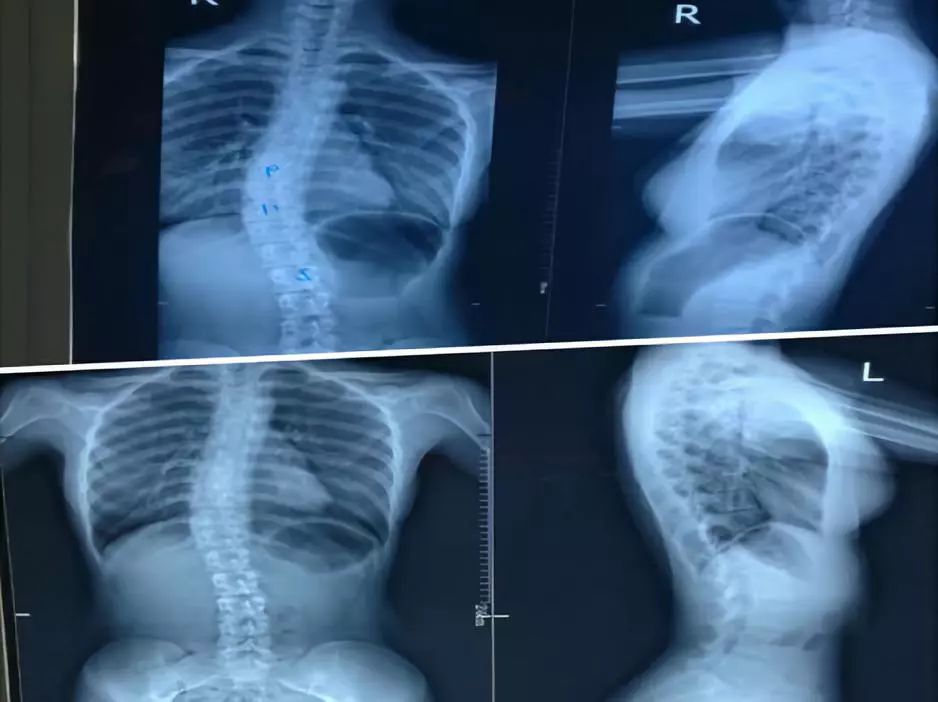

18岁王小妹脊柱侧弯后,在家人的陪同下来到深圳市中医院推拿科就诊,专家为王小妹制定了治疗方案,经过三周的治疗时间,脊柱侧弯角度减小(Cobb角度23°—16°)。